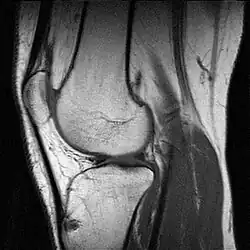

MR-Aufnahme eines menschlichen Kniegelenks

Siehe Magnetresonanztomographie, Vorteile: wie CT, dabei besserer Weichteilkontrast, keine ionisierenden Strahlen, aber höherer zeitlicher und apparativer Aufwand, höhere Kosten, geringere Toleranz beim Patienten vor allem Klaustrophobie bei herkömmlichen Geräten, neueres Design ermöglicht offenere Geräte mit guter Patientenakzeptanz, Kontrastmittel zum Beispiel Gadoliniumverbindungen und superparamagnetische Eisenoxid-Partikel.